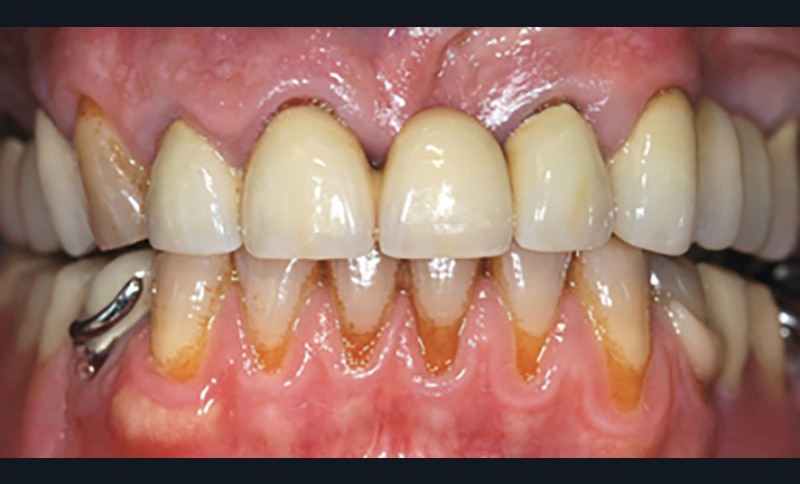

Il débute par l’évaluation des paramètres gingivaux (ligne du sourire [2], biotype parodontal [3], présence ou absence de papilles interdentaires, alignement des collets…). Les paramètres dentaires (origine de l’édentement, état de restauration des dents adjacentes, forme des couronnes dentaires…) compléteront cet examen (fig. 1). L’origine de l’édentement ne doit pas être sous-estimée. Graetz et al. [4] ont démontré que les patients avec des antécédents de maladie parodontale avaient une perte osseuse marginale et des profondeurs de poches plus importantes que les patients avec un parodonte sain.